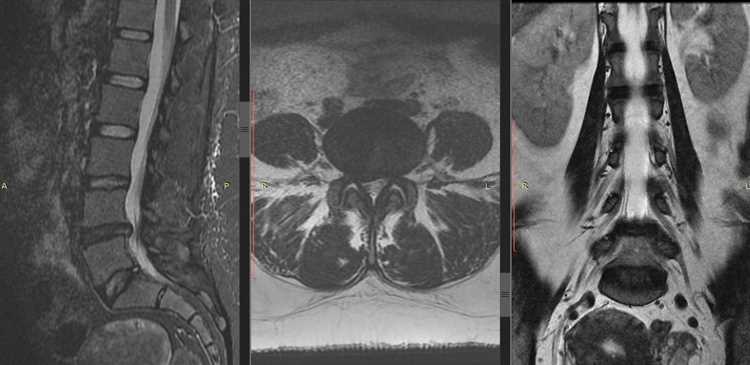

Микрохирургическая дискэктомия — операция проводится со спины через небольшой разрез. Под операционным микроскопом удаляется грыжа диска и освобождается сдавленный корешок. Затем производится ушивание раны. Клинический пример экстрафораминальной грыжи на уровне L4-5 справа.